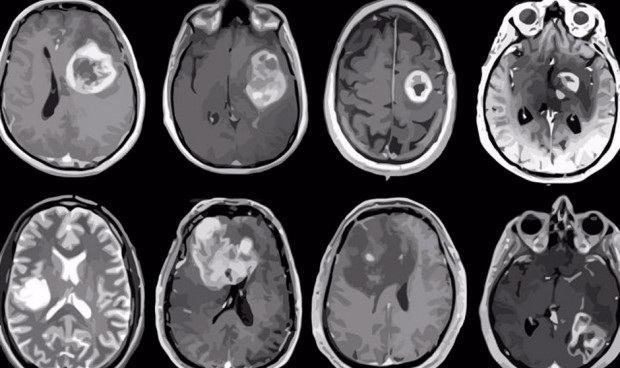

Una investigación de la Universidad de Bristol (Reino Unido) ha desarrollado un sencillo análisis de sangre para detectar los glioblastomas (GBM), que podría suponer un diagnóstico más temprano y opciones de tratamiento más eficaces y personalizadas de este tumor, el tipo más común de cáncer cerebral maligno.

En este estudio se desarrollaron modelos matemáticos y se emparejaron con datos experimentales. Los investigadores descubrieron que, para el biomarcador prospectivo del GBM, la proteína ácida fibrilar glial (GFAP), la reducción del umbral actual del biomarcador podría conducir a una detección más temprana de los GBM.

"Nuestros hallazgos proporcionan la base para obtener más datos clínicos sobre el impacto de la reducción del umbral de detección actual del biomarcador conocido, GFAP, para permitir una detección más temprana de los GBM mediante análisis de sangre. Con más datos experimentales, también puede ser posible cuantificar las heterogeneidades de los tumores y de los pacientes e incorporar los errores en nuestros modelos y predicciones de los niveles en sangre para diferentes tumores. También hemos demostrado cómo nuestros modelos pueden combinarse con otros diagnósticos, como las exploraciones, para mejorar la visión clínica con vistas a desarrollar tratamientos más personalizados y eficaces", ha detallado Johanna Blee, autora principal del estudio e investigadora asociada del Departamento de Ingeniería Matemática de la Universidad de Bristol.